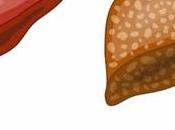

Fatty Liver

The liver is the second largest, reddish–brown organ on the right side of the belly which feels rubbery to the touch. Weighing about 3 pounds, It performs... Read more